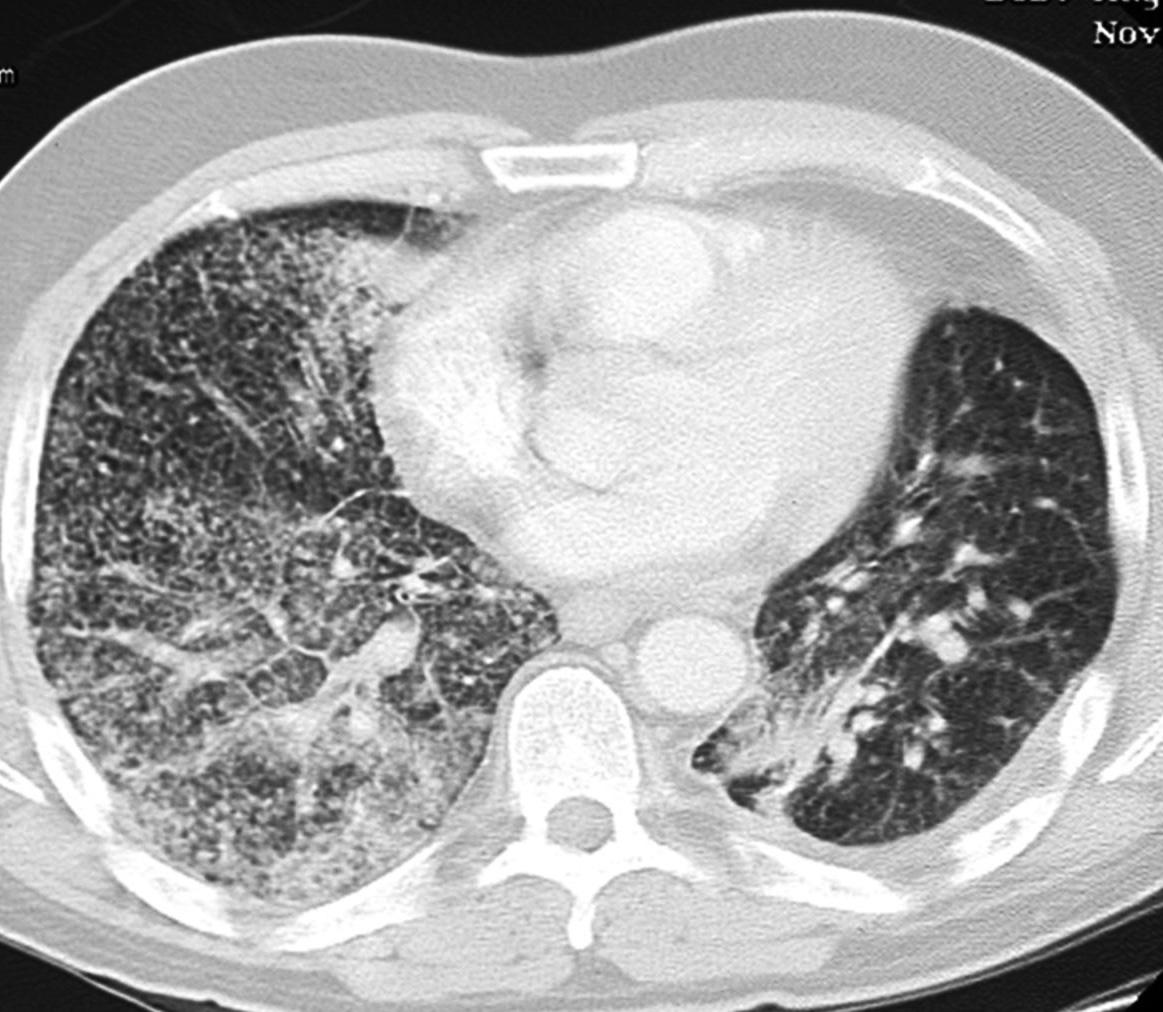

Рентгеносемиотика диссеминированного туберкулеза легких зависит от клинической формы заболевания. Признаками острого процесса служат наличие в обоих легочных полях множественных однотипных очагов, расположенных симметрично, в виде цепочки по ходу сосудов. При подострой диссеминации очаги имеют тенденцию к слиянию, возможно образование полостей распада. Для хронической диссеминации характерно асимметричное расположение очаговых теней, которые имеют разную форму, величину, очертания, интенсивность в зависимости от срока давности их возникновения. Рентгенография легких, как правило, дополняется линейной или компьютерной томографией.

КТ при бронхиолоальвеолярном раке. Множественные хаотичные очаги, чередующиеся с участками уплотнения по типу матового стекла, фокусами альвеолярной консолидации.